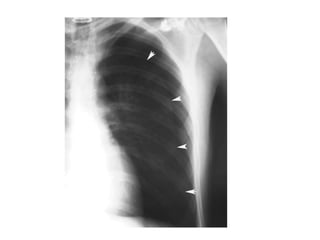

Derrame pleural tipico